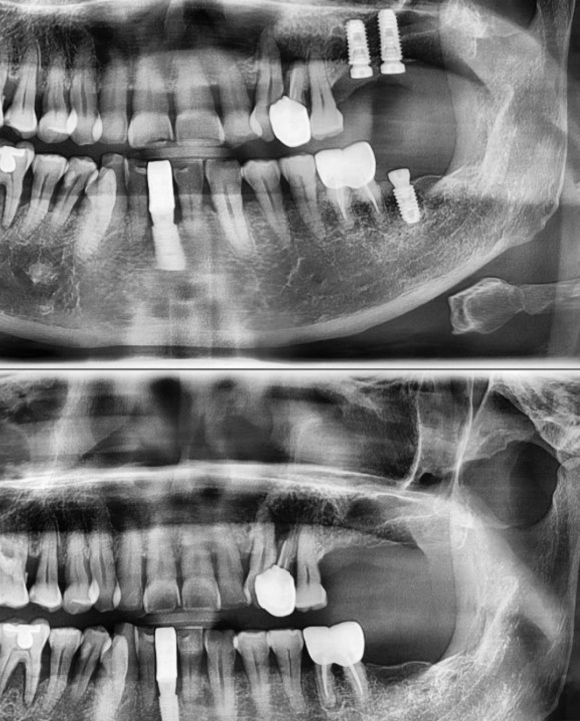

2022.4.13 오전첫환자 임플란트3개

저희 숭실대 입구역 리더스진 치과는 한달 평균 임플란트 60~100개를 꼼수 없이 가장 좋은 재료와 기술로 원칙적으로 식립하는 치과입니다.